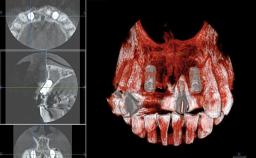

In 2001, a 48-year-old woman presented at a dental clinic with a failing fixed partial denture spanning from teeth 13 to 21. She was experiencing pain upon function, tenderness to palpation facial to tooth 13, and severe mobility of the prosthesis. Radiographic and clinical assessment revealed a subcrestal fracture of tooth 13, making its restoration unlikely. It was determined by the clinician that the tooth needed to be extracted prior to proceeding any further with dental care. After the extraction, the patient lost confidence in the progression of her treatment and sought consultation at the Center for Implant Dentistry. At her consultation visit in our clinic, an extra- and intraoral clinical examination revealed a medium lip line at full smile and an edentulous area spanning from 13 to 12 with both vertical and horizontal deficits in hard and soft tissue.

# of Implants 2

Type of Implants One-Piece|Reduced-Diameter

Bone Augmentation Horizontal|Staged|Vertical

Bone Volume Deficient vertically or deficient vertically AND horizontally